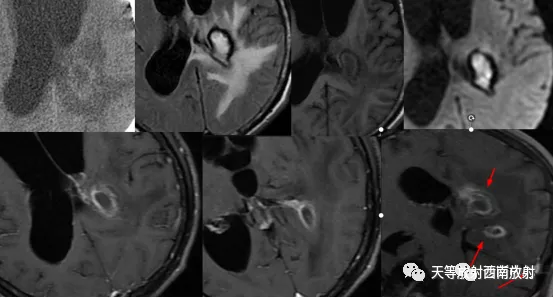

▲病例:脑淋巴瘤。脑深部结节病灶,具有刀切征、凹陷征或肚脐凹征、尖角、多发。DWI呈稍高信号,形态上怪异,波普NAA及Cho减低,出现导致LL峰。颈部、胸廓入口区及腋窝多发淋巴结肿大并相互融合。

▲病例:脑淋巴瘤。右侧深部脑实质内结节状异常信号,伴周围大面积水肿区,增强扫描呈环状强化。(病例来源东南大学附属中大医院医学影像科)

▲图 脑出血,治疗后期,脑压增高,脑积水,颅内感染性病变。增强扫描显示多灶性及多发环状强化。